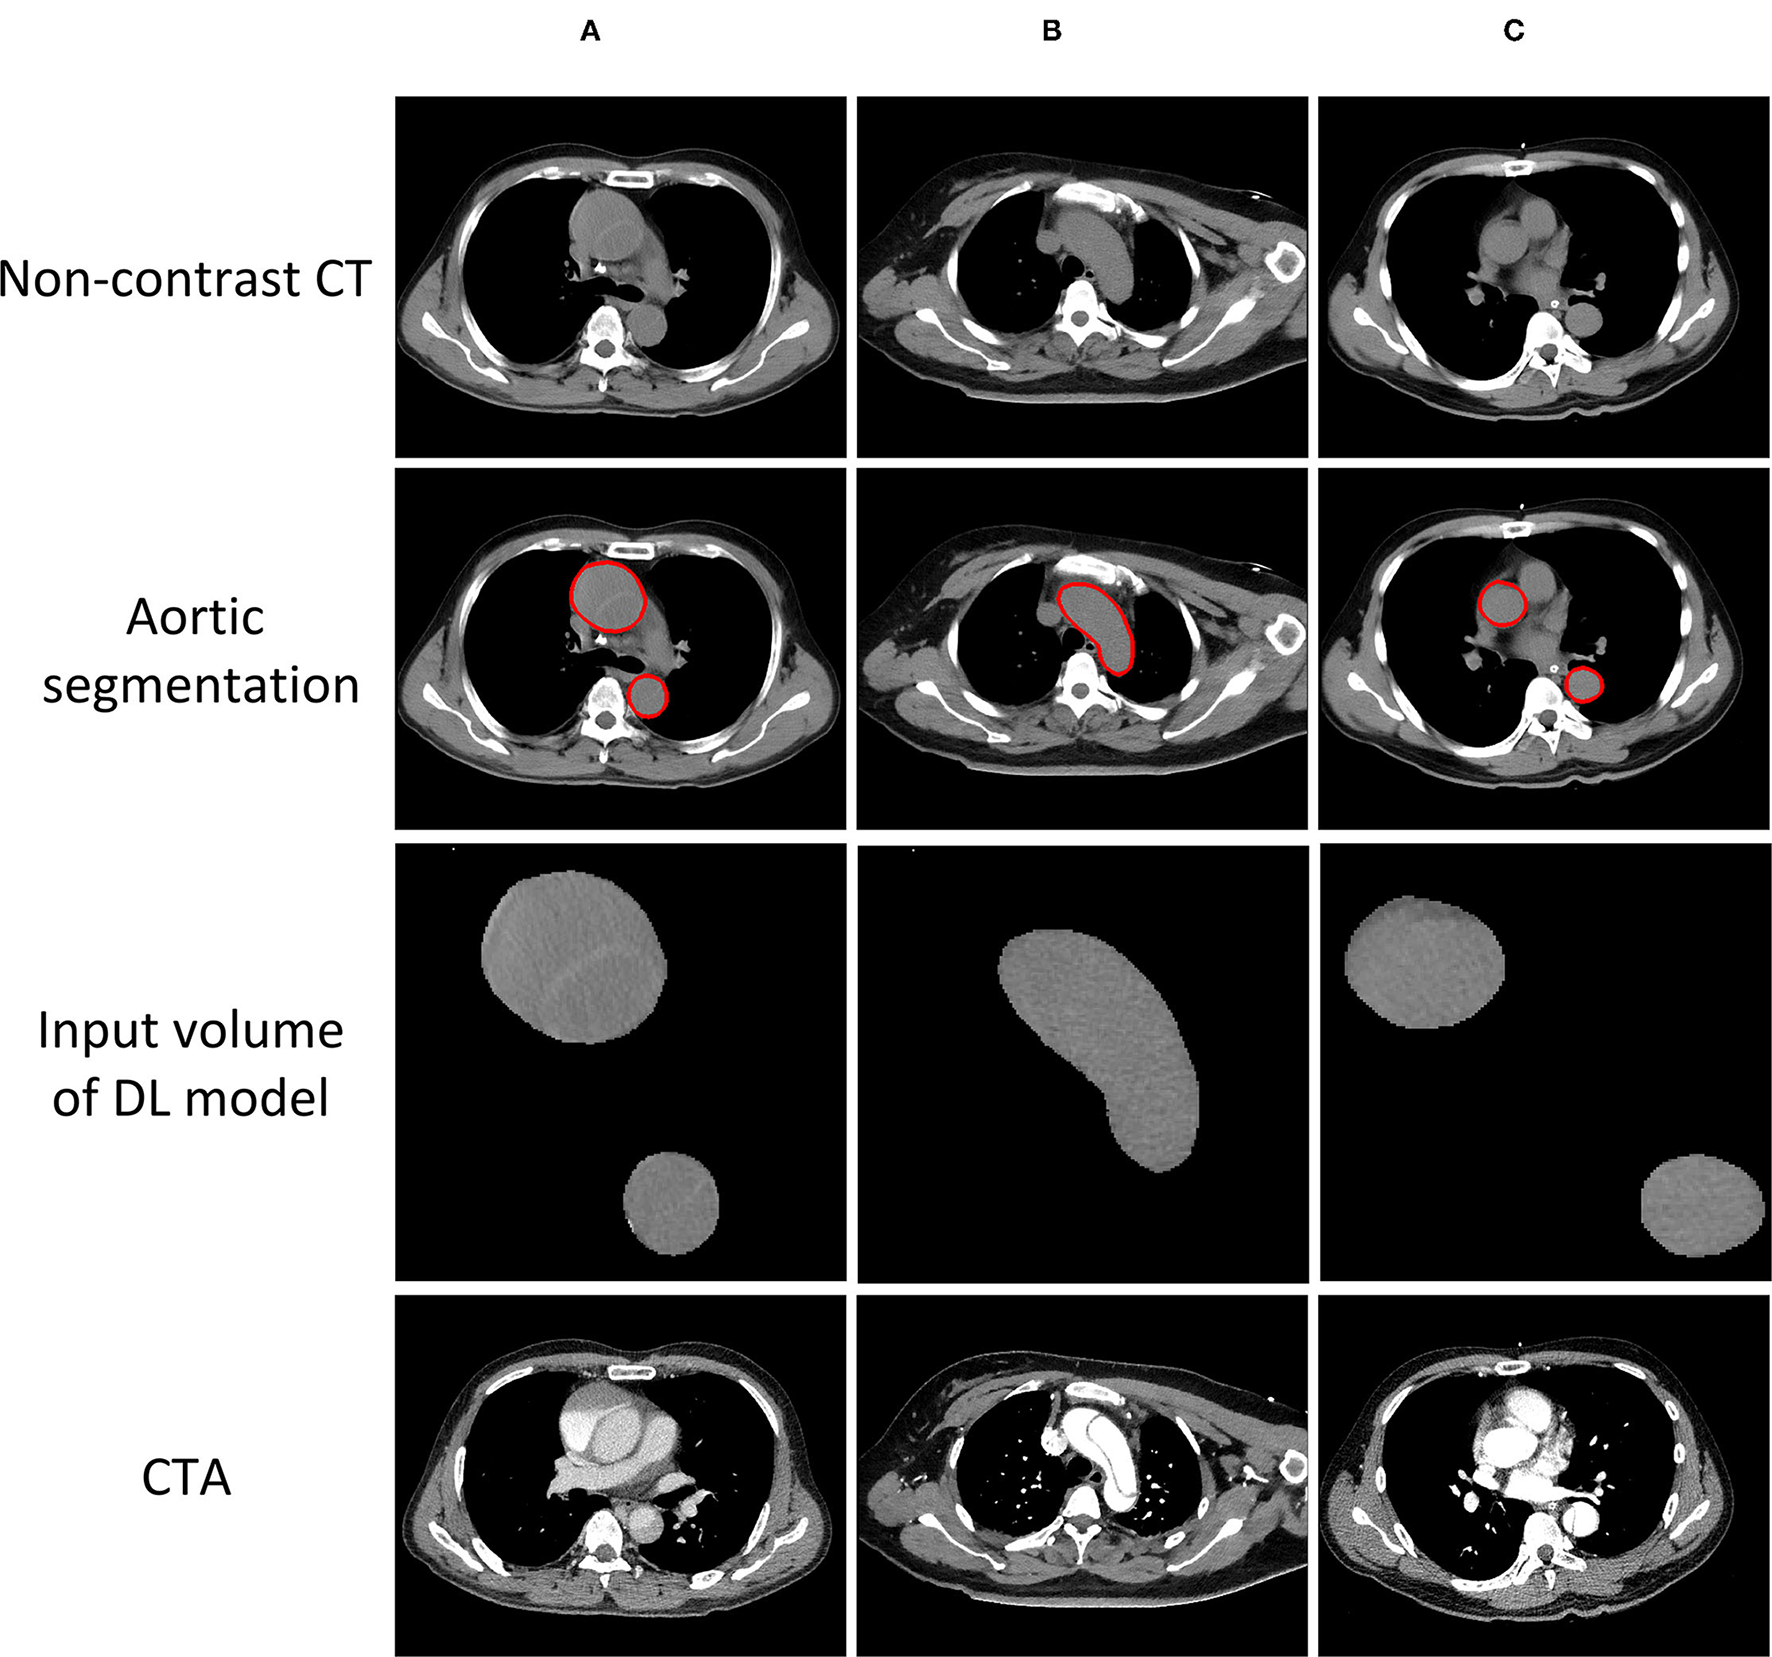

Figure 6

AD cases with CT images. (A) Successfully detected by all the radiologists and the model. (B) Successfully detected by our model, but neglected by one of the radiologists. (C) Neglected by both our model and all the radiologists.